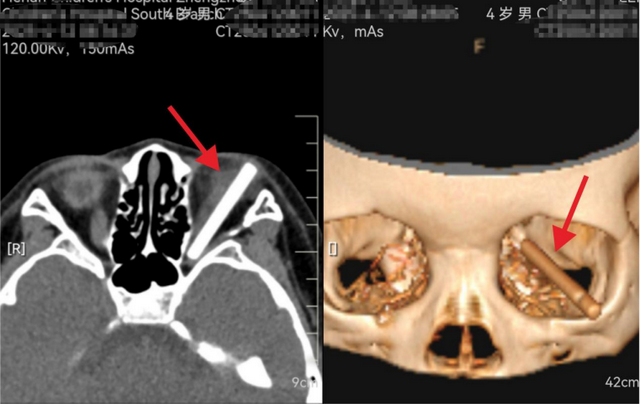

在CT影像来看,磊磊的左眼眶内可以看到一个非常明显的杆状异物,比眼球还长,斜插在眼眶内。其大小、位置、嵌入时长着实让人看着瑟瑟发抖。

手术室里,医护人员屏息凝神,李玉军院长在显微镜下小心翼翼,试图将异物尽快取出。最终,在不损伤周围组织的情况下,李院长顺利的从磊磊眼里取出了一根长约40毫米,直径约5毫米,疑似塑料的硬质异物。